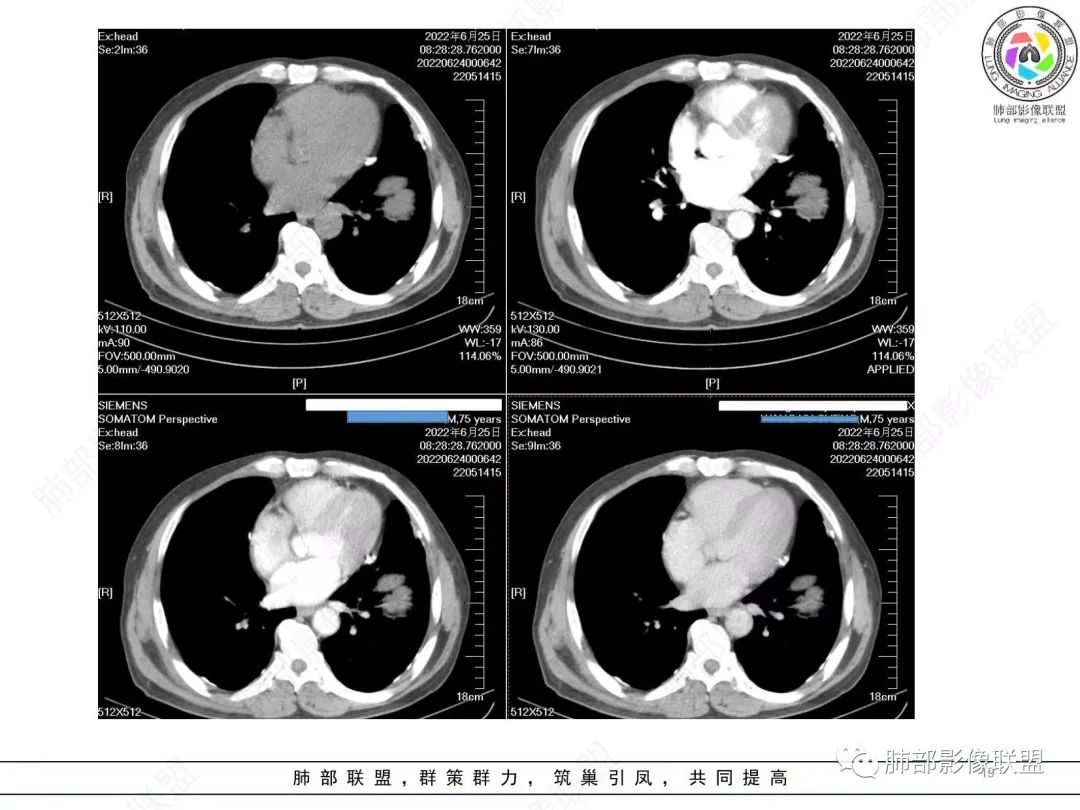

糖尿病史,慢性病程,左肺巨大肿块,跨叶生长,肿块近端可见充气支气管征及悬浮气泡,轻度圴匀强化,病变长轴与胸膜平行,炎性标志物正常,考虑放线菌,其次淋巴瘤

我要修正一下观点了:仔细看了视频,肿块占位效应明显,对周围血管,支气管有推挤,增强后强化不明显,NSE增高,半年体重下降25公斤,虽然有内部支气管扩张,血管漂浮,边界清楚支持淋巴瘤,但强化太低,膨隆,占位推挤太明显(淋巴瘤一般没有这么明显的占位效应),胸膜关系有载桩,恶病质明显(乏力,半年体重下降了25公斤),NSE也明显增高,就不支持淋巴瘤了。还是考虑外朝内的恶性肿瘤,间质来源的肉瘤伴有神经内分泌分化或者大神泌。

不支持淋巴瘤的有四点:1、对周围血管支气管推挤明显。2、胸膜有栽桩,3、强化太弱(淋巴瘤一般还是中度以上甚至高度强化多见),4、NSE升高明显,体重下降太明显。

腺癌一般不会有这么明显的推挤作用的。

支气管不像淋巴瘤,肺动脉走也不连续。支气管是断断续续的堵塞和扩张,狭窄。不是那种扩张

老年男性,糖尿病病史,消瘦、乏力三个月,肿瘤标志物高。左肺上叶胸膜下肿块,边界清晰,可见支气管影及坏死区,增强病灶边缘强化,内部未见明显强化,邻近胸膜有累及,考虑恶性,建议穿刺活检。

左肺紧贴胸膜巨大肿块,跨叶裂生长,密度均匀,边缘清晰,内支气管略扩张,增强见血管影,强化不明显,胸膜栽赃,钙化,考虑淋巴瘤。

我再建一下血管。支气管进入,但是近端推移,堵塞

大肿块,边缘光滑,深分叶

近端支气管堵塞、推移为主

部分类似于脐凹征

内部支气管扩张

肺动脉推移为主,边缘部分进入

淋巴瘤符合吗?